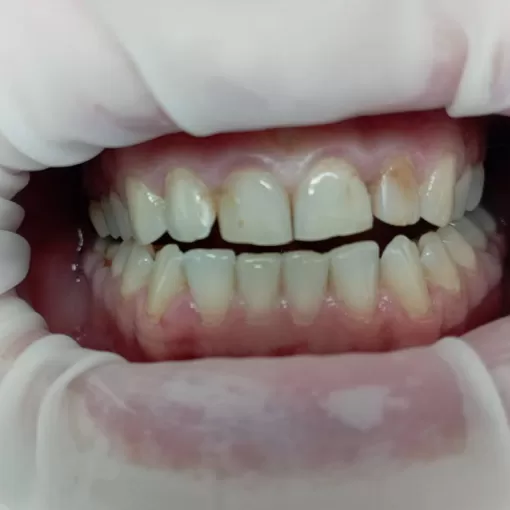

По данным КЛКТ в области зуба 4.6 был выявлен воспалительный очаг. Проведено эндодонтическое лечение с использованием микроскопа, с последующим протезированием коронкой из диоксида циркония.